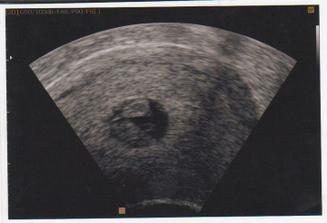

Taááákže 2. KET při 3. IVF